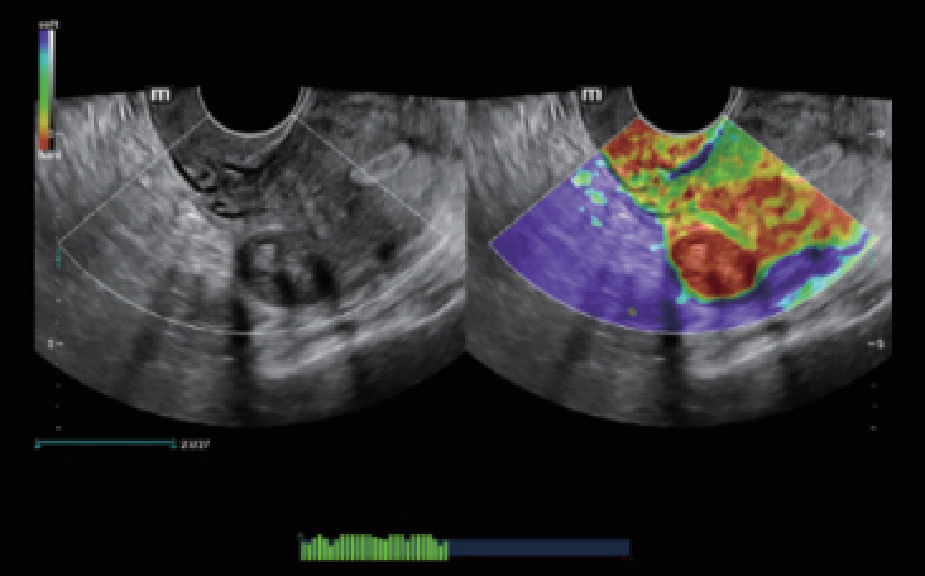

Le Nuewa?I9, con?u spÃĐcialement pour la santÃĐ de la femme et les soins nÃĐonataux, offre une expÃĐrience entiÃĻrement nouvelle gr?ce aux innovations dont il est dotÃĐ, tant à lâintÃĐrieur quâà lâextÃĐrieur. Ces innovations sont dÃĐveloppÃĐes sur la base d'une comprÃĐhension approfondie de scÃĐnarios cliniques complexes, fournissant des rÃĐponses prÃĐcises et adaptÃĐes ainsi qu'une efficacitÃĐ exceptionnelle et une expÃĐrience utilisateur remarquable.

Solution complÃĻte gr?ce au ZST +

La plate-forme ZST+?est une innovation extraordinaire, reprÃĐsentant une ÃĐvolution de lâimagerie ultrasonore. Elle transforme la formation conventionnelle de faisceaux en un traitement basÃĐ sur les canaux de donnÃĐes. Elle repousse les limites de lâimagerie conventionnelle et du compromis entre rÃĐsolution spatiale, rÃĐsolution temporelle et uniformitÃĐ tissulaire en offrant une qualitÃĐ dâimage exceptionnelle pour des solutions dâimagerie infinies et en constante ÃĐvolution.